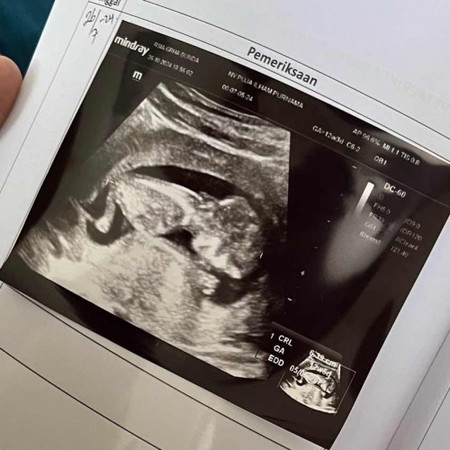

Kehamilan 12 week

Kemarin pas USG bentukannya sudah seperti ini 🥰🥰 Belum bisa diliat jenis kelaminnya, katanya bulan depan pas 16w

Sama bun usg 12 weeks janin persis bentuknya kaya gitu udah gerak-gerak juga lincah banget

bun itu USG yg 2D apa bukan kok bisa jelas bgt yh

Yg 2D bun, iyaaa udah jelasss kalo usia segini